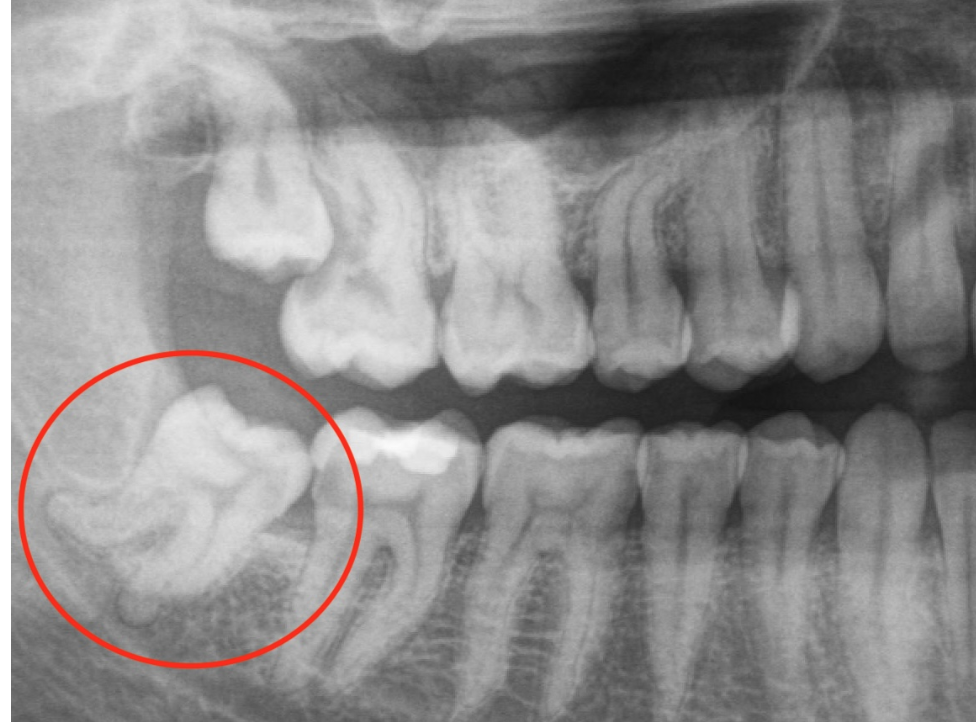

Zähne ziehen aus Platzmangel vermeiden mit natürlicher Gaumenerweiterung